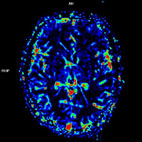

磁振造影大腦組織灌流影像,可看出腦組織血液灌流的生理狀況。